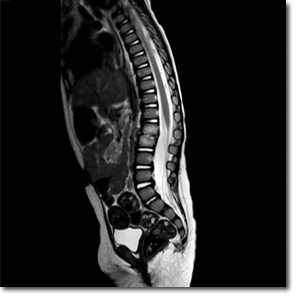

I­rri­ta­bi­li­dad y al­te­ra­ción de la mar­cha, ¿en qué de­be­mos pen­sar?

Niña de 15 meses, sin antecedentes médico-quirúrgicos de interés, que acude por irritabilidad, rechazo de deambulación y sedestación de 2 semanas de evolución asociado a estreñimiento de 4 días. Afebril en todo momento. A la exploración destaca dolor a la palpación en apófisis espinosas lumbares. A la deambulación adopta una postura antiálgica con hiperlordosis.